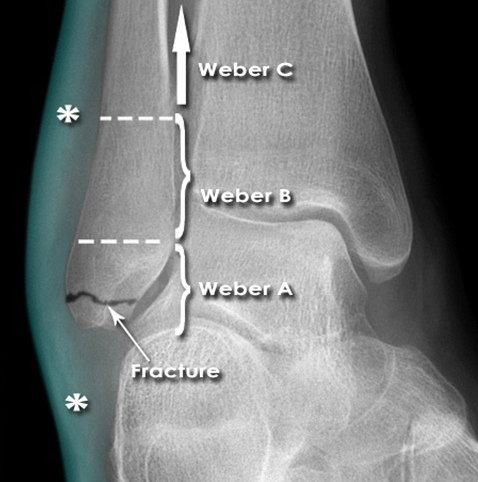

Explore Weber A ankle fractures: extra-articular fibula fractures below the syndesmosis. Understand their sta…

Explore the Danis-Weber classification for ankle fractures, its historical context, and critical surgical ana…